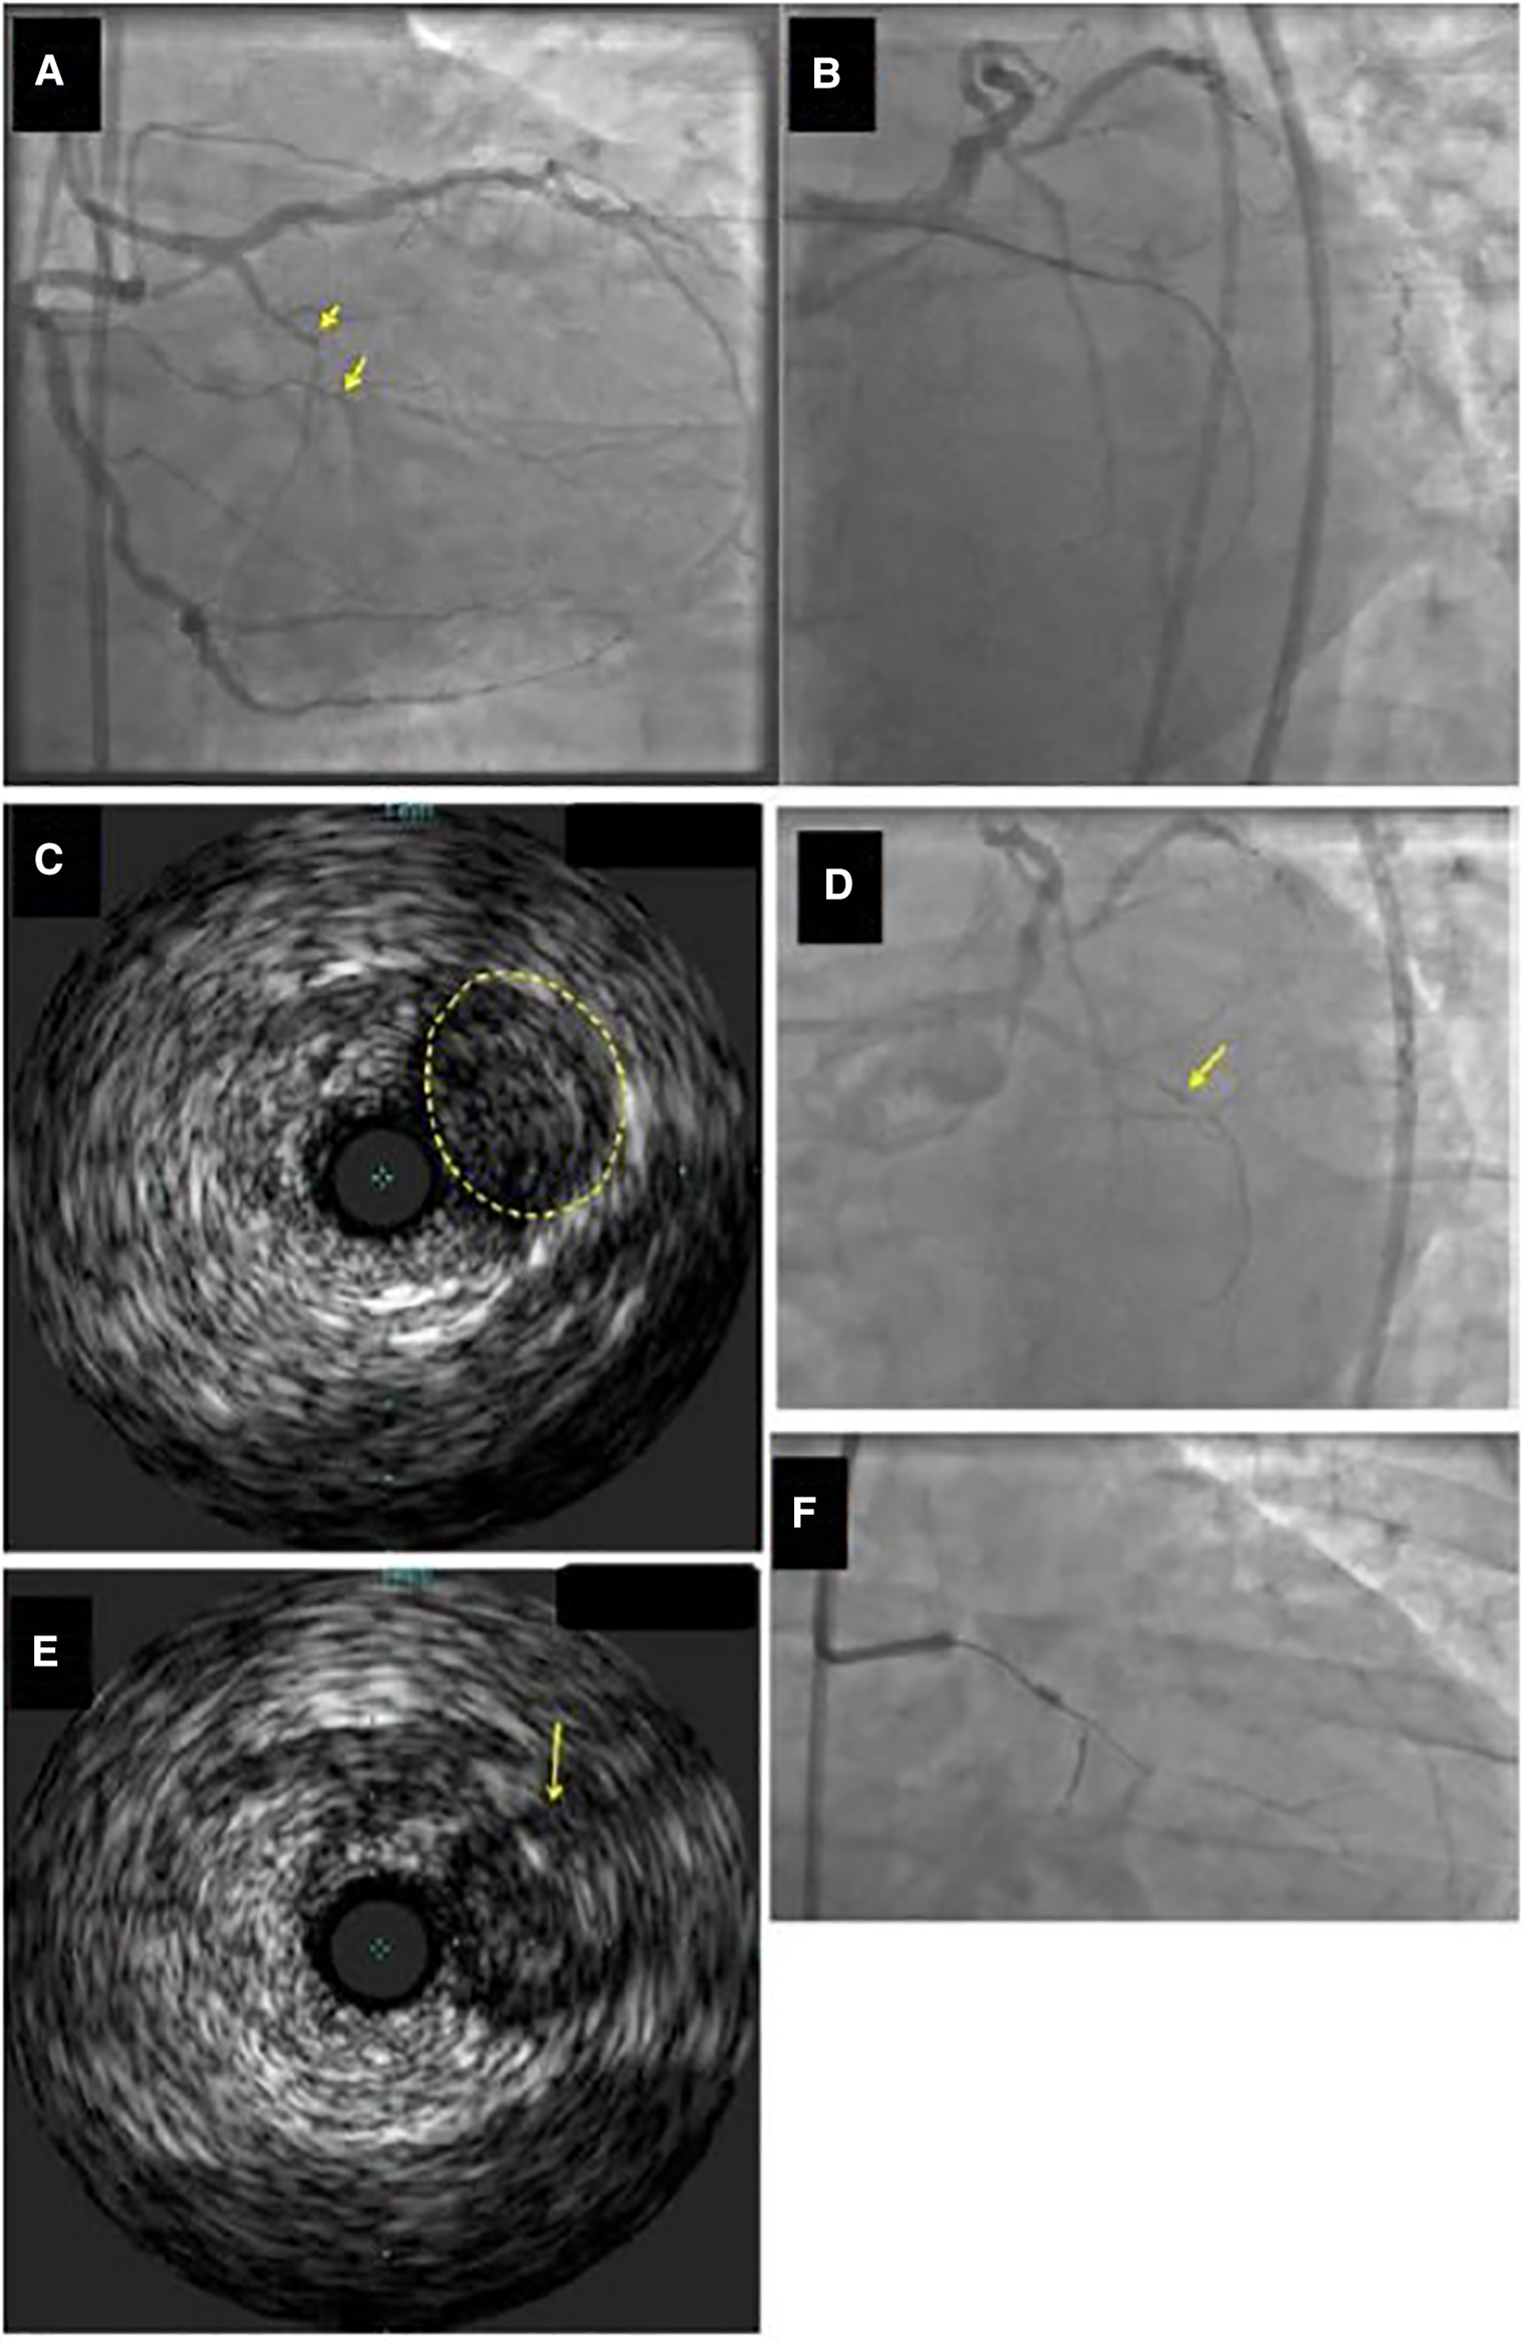

Figure 3

Example of identification of the proximal cap location by intravascular ultrasound (IVUS). (Panel A) Ostial chronic total occlusion (CTO) of the first obtuse marginal branch (arrow). (Panel B) The guidewire kept entering the distal circumflex during antegrade wire escalation approach. (Panel C,D) IVUS demonstrated that the CTO (yellow circle in Panel C) originated proximal (arrow in Panel D) to the distal circumflex's apparent origin. (Panel E) A Confianza Pro 12 guidewire was used for antegrade crossing and its location within the CTO was confirmed by IVUS. (Panel F) Confianza Pro 12 was advanced through the occlusion. Modified with permission from Brilakis ES. Manual of chronic total occlusion interventions a step-by-step approach. Second edition. ed. London: Elsevier/Academic Press; 2018.